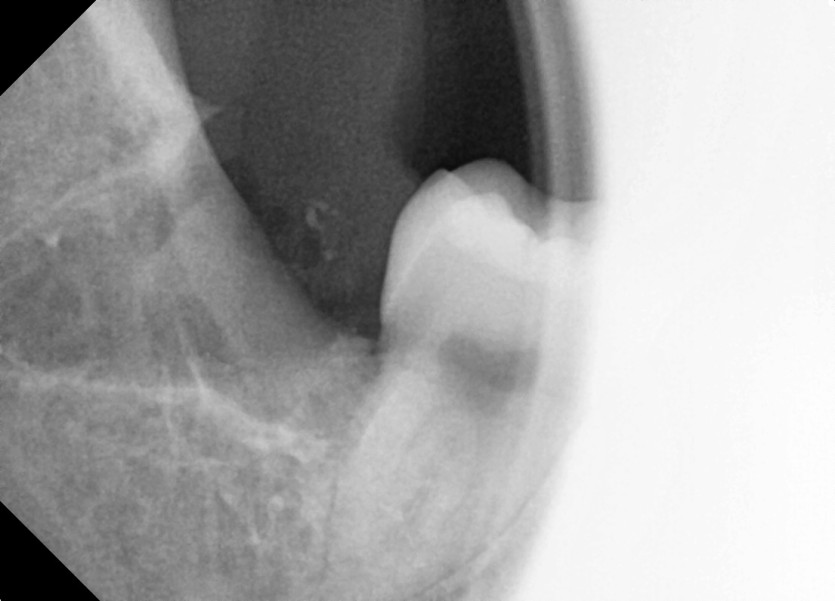

#48 사랑니 발치

구강 외과 전문의가 당일 발치했습니다.